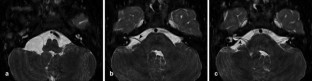

Facial nerve palsy in posterior fossa arachnoid cysts: report of two cases

Two patients with a posterior fossa arachnoid cyst responsible for isolated facial nerve palsy are reported.

The relationships between the cyst and the facial nerve and between the facial nerve palsy and the size variation of the cyst are discussed and documented by pre- and postoperative magnetic resonance imaging.

Fig. 2